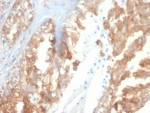

CRYAB Antibody Tumor Stress IHC. Immunohistochemistry of Alpha B crystallin / CRYAB in FFPE human renal cell carcinoma tissue using mouse monoclonal CRYAB antibody, clone CRYAB/4659. HRP-DAB brown staining highlights cytoplasmic labeling of malignant epithelial cells, with variable intensity consistent with stress-associated expression in tumor tissue, while surrounding stromal elements show reduced staining and nuclei are counterstained blue. Heat induced epitope retrieval was performed by boiling tissue sections in pH 9 10 mM Tris with 1 mM EDTA for 20 min followed by cooling prior to staining.